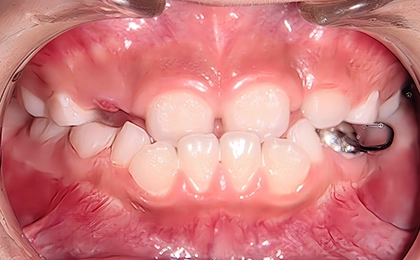

Case3 前歯の受け口

Before

治療内容 | 前歯の受け口をリンガルアーチで改善後、上下の前歯にブラケットを装着し、デコボコの治療を行い、永久歯列に生え変わるまで経過観察をしました。 |

治療のリスク | 前歯の受け口が残ったままだと骨格性の受け口が助長され、将来的に手術併用による外科矯正治療のリスクが上がってしまいます。 |